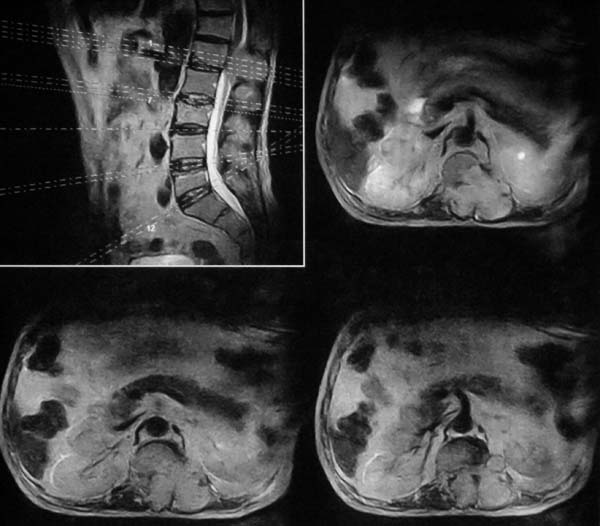

病史特点:

1.中年男性

2.腰疼,双下肢麻木1月。

3.ct 可右肾上腺占位,腰1椎体及附件可见骨质破坏及软组织肿块。

4.mri:腰1椎体及附件t1wi低信号,t2wi高信号。

考虑右侧肾上腺癌骨转移.或右肾上腺及骨均为转移瘤。